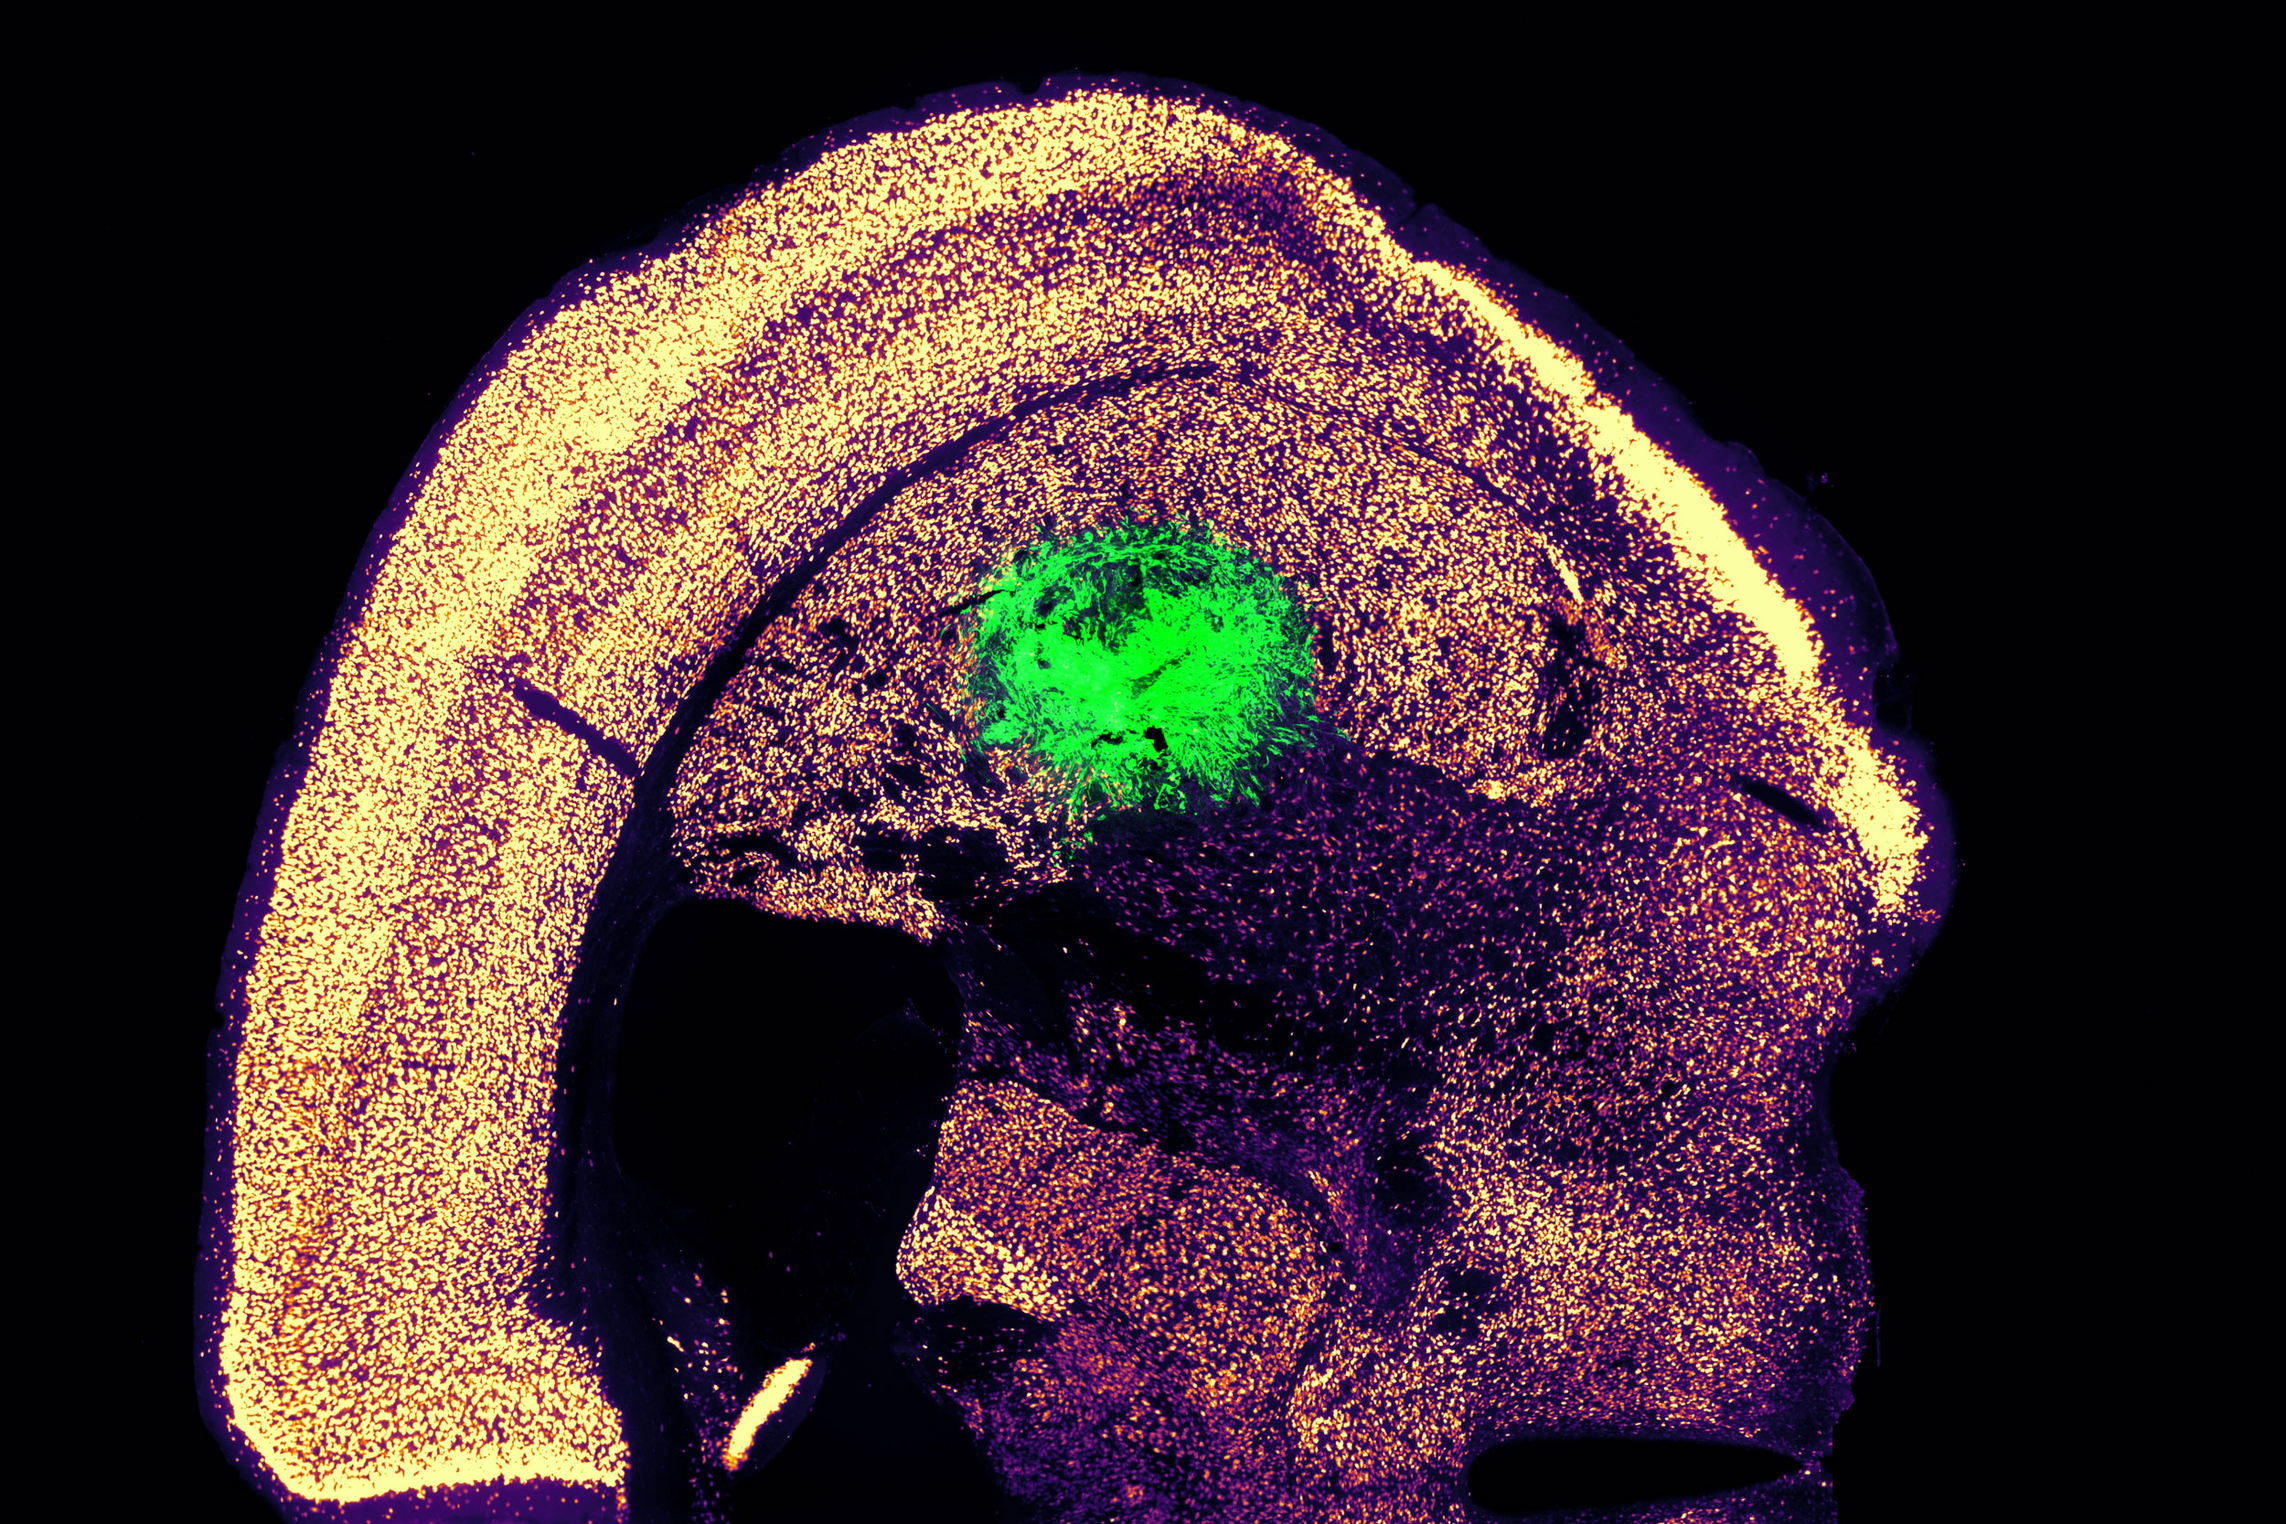

Working with colleagues at Boston University, the researchers then tested whether these motor neurons could be successfully engrafted into mice. They delivered the cells to a part of the brain known as the striatum, which is involved in motor control and other functions.

After two weeks, the researchers found that many of the neurons had survived and seemed to be forming connections with other brain cells. When grown in a dish, these cells showed measurable electrical activity and calcium signaling, suggesting the ability to communicate with other neurons. The researchers now hope to explore the possibility of implanting these neurons into the spinal cord.